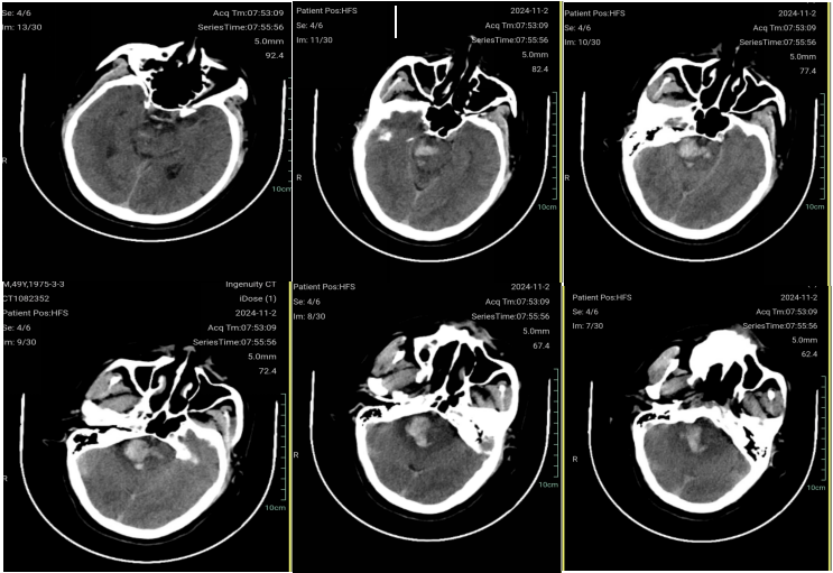

术前CT

脑干出血

- 高血压性脑干出血?

- 高血压性脑干出血:有高血压病史,发病后血压253/110mmHg。

- 海绵状血管瘤破裂:血肿的形状圆钝,与高血压性撕裂性不全一致,不能排除海绵状血管瘤导致。

- 动静脉畸形破裂:脑干实质内小的血管畸形也不能排除。

(注:患者疾病进展迅速,快速进入昏迷状态,鼾式呼吸,突发呼吸停止风险极高,需紧急手术清除血肿减压,磁共振和DSA等检查无法完成,准确诊断比较困难,需术中探查)

- CT示脑干血肿量较多,接近10ml,占位效应明显